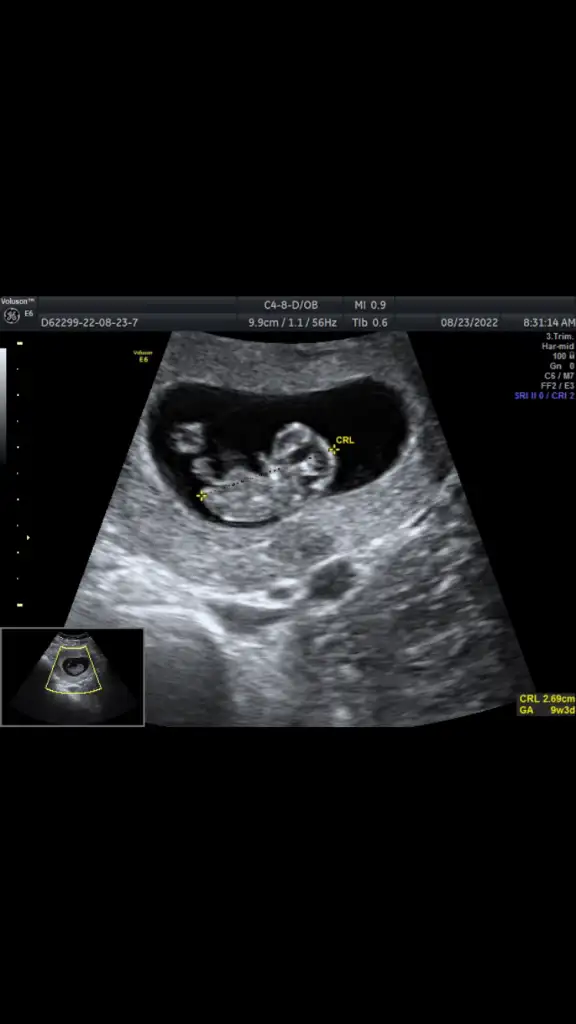

BEnce kizEki Görüntüle 3121894 banada tahminde bulunun